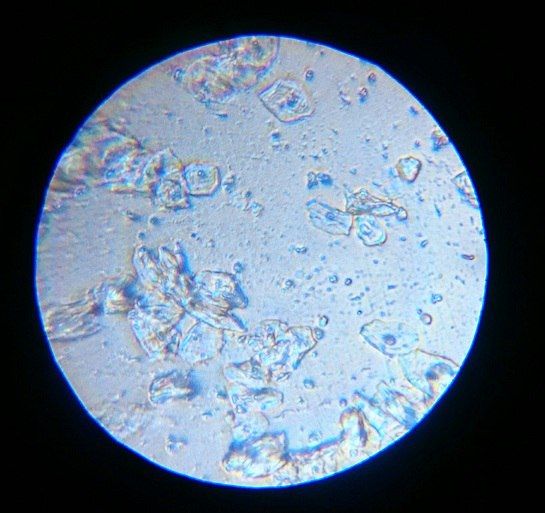

Полоска вроде не там где должна быть?

Полоска вроде не там где должна быть?

Я читала, что тесты на о показывают б. Возможно ли что и микроскоп на о, показал б.

Я уже ловила о в этом цикле, а по бт поймала из, ну как я думала, как тут вдруг. Вторая о или это первый признак б. Давайте попробуем разобраться. Подобного я р